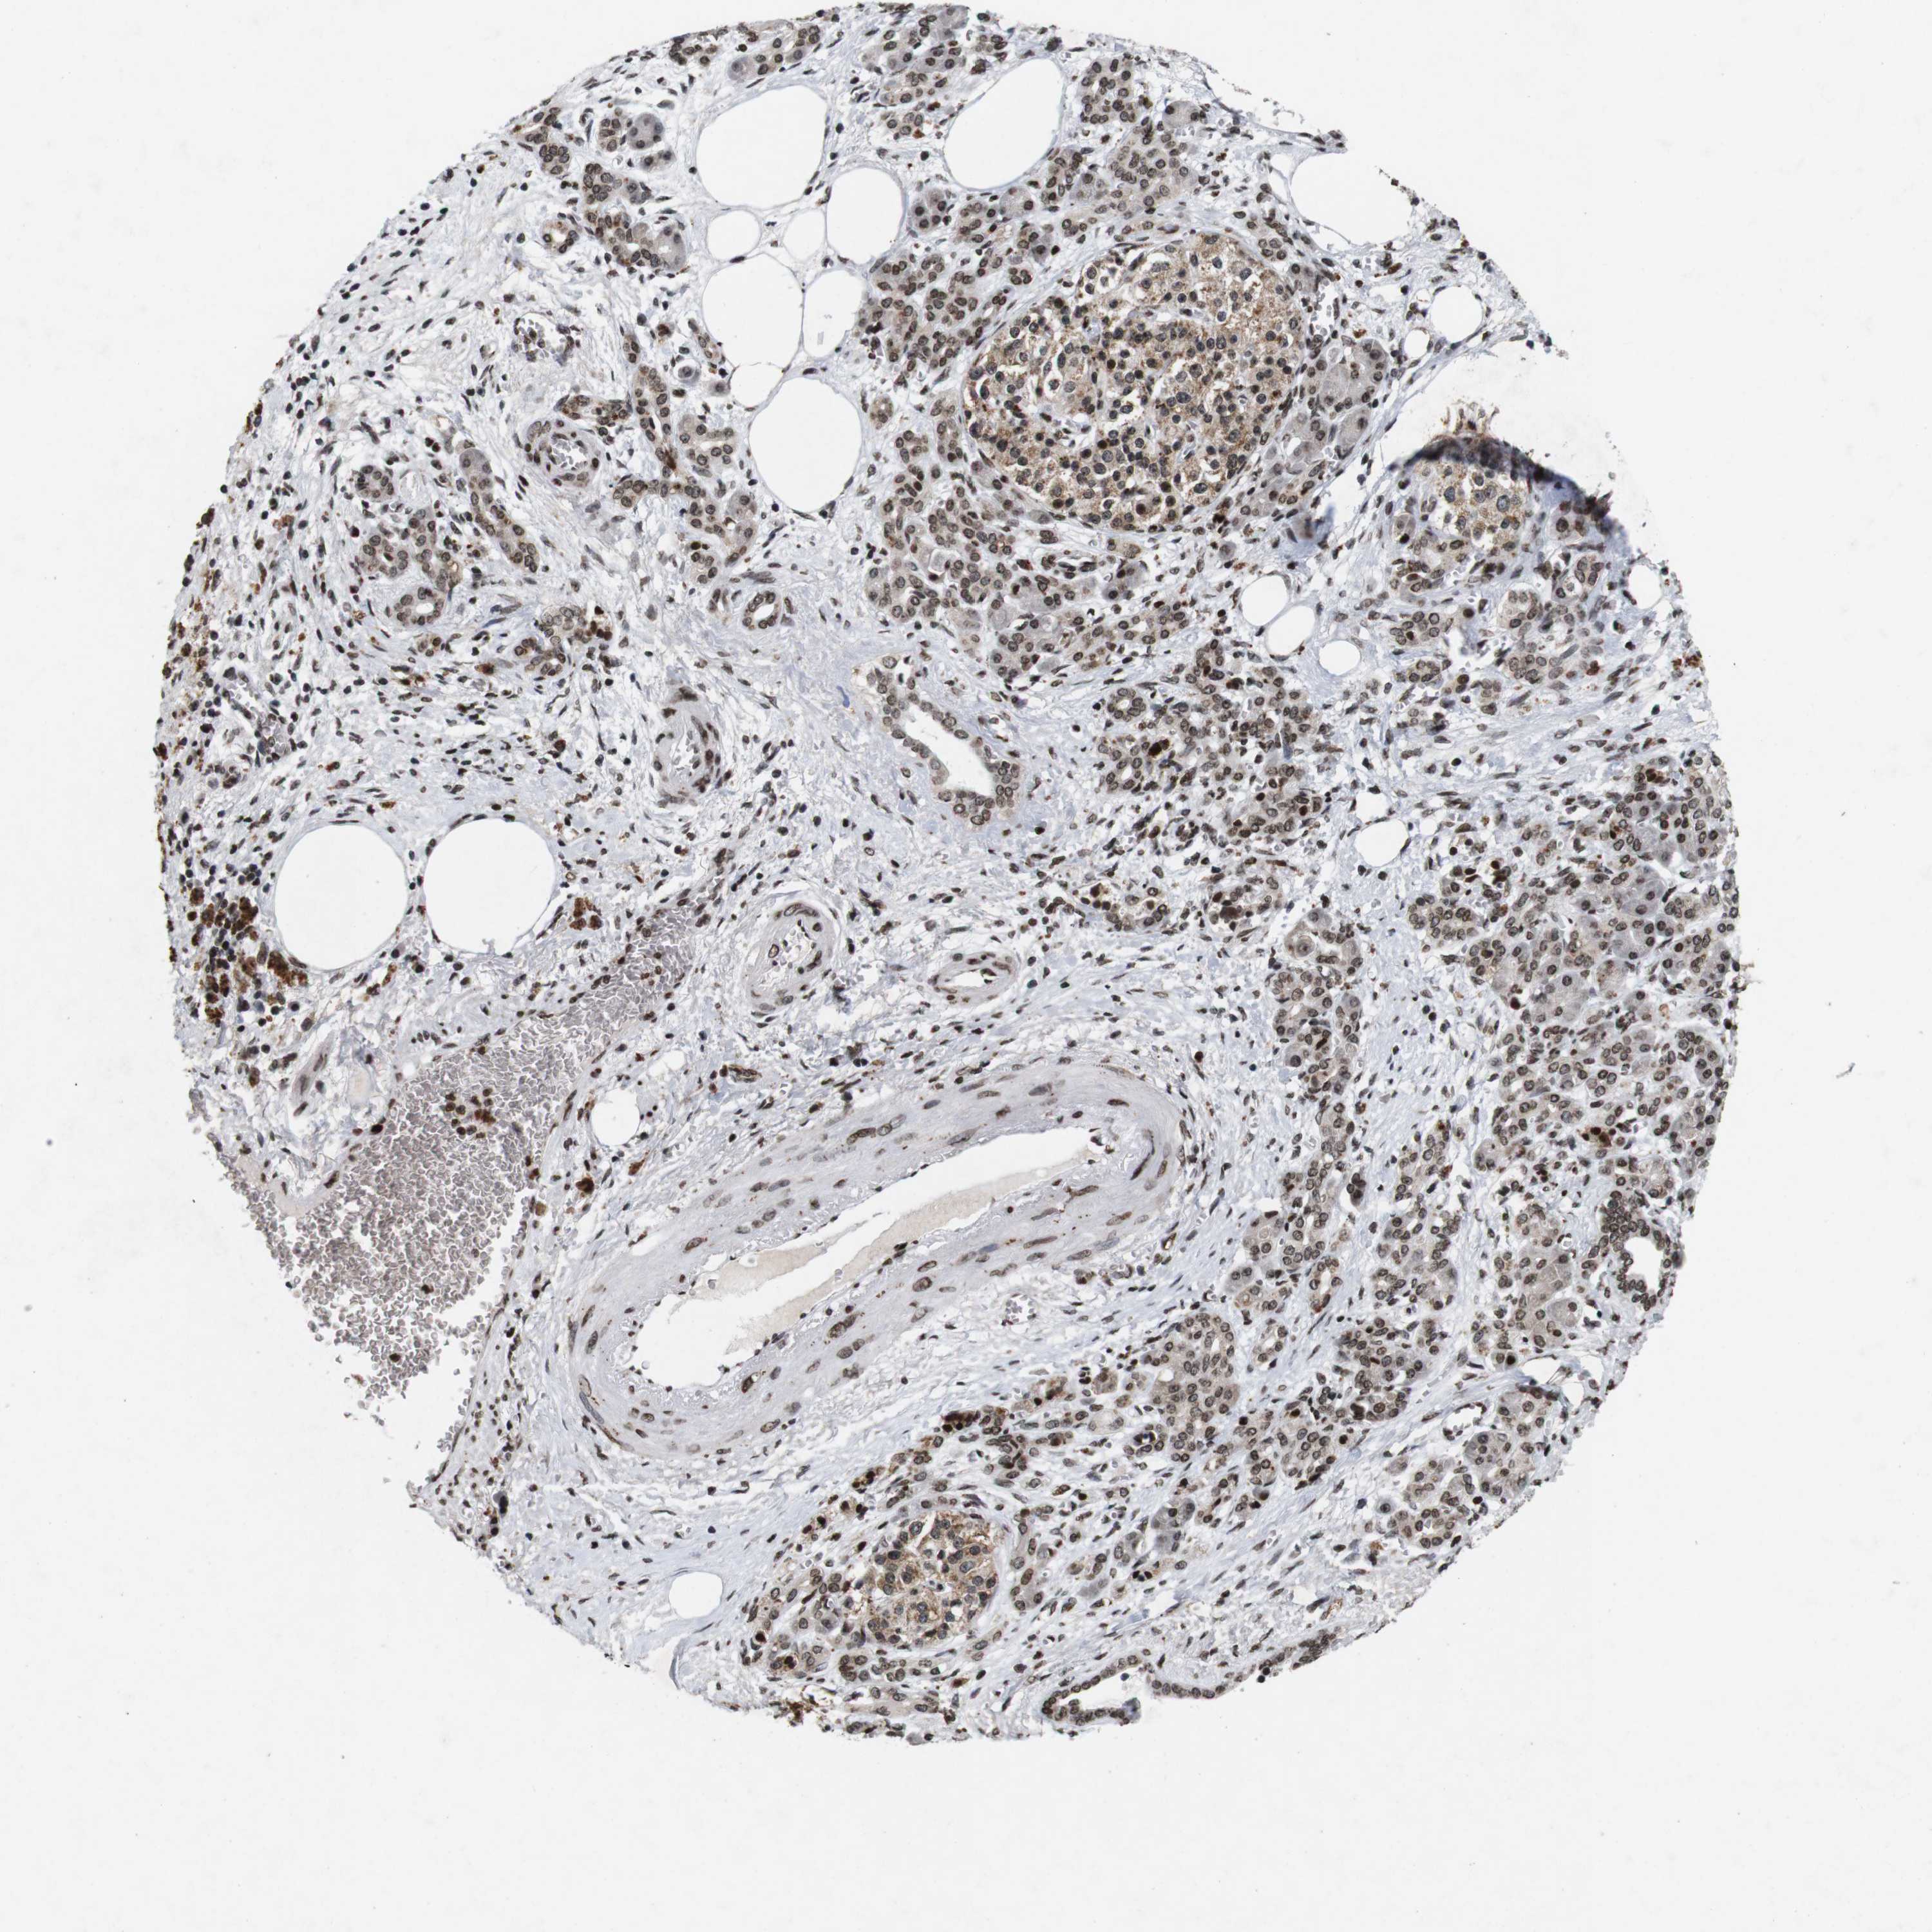

PANCREATIC CANCER - Protein expressioni

A mouse-over function shows sample information and annotation data. Click on an image to view it in a full screen mode. Samples can be filtered based on level of antibody staining by selecting one or several of the following categories: high, medium, low and not detected. The assay and annotation is described here.

Note that samples used for immunohistochemistry by the Human Protein Atlas do not correspond to samples in the TCGA dataset.

Antibody stainingi

Antibody staining in the annotated cell types in the current human tissue is reported as not detected, low, medium, or high, based on conventional immunohistochemistry profiling in selected tissues. This score is based on the combination of the staining intensity and fraction of stained cells.

Each image is clickable and will lead to virtual microscopy that enables deeper exploration of all samples and also displays staining intensity scores, fraction scores and subcellular localization as well as patient and tissue information for each sample.

Antibody HPA011324

Staining

High

Medium

Low

Not detected

Intensity

Strong

Moderate

Weak

Negative

Quantity

>75%

75%-25%

<25%

None

Location

Nuclear

Cytoplasmic/membranous

Cytoplasmic/membranous,nuclear

Adenocarcinoma, NOS